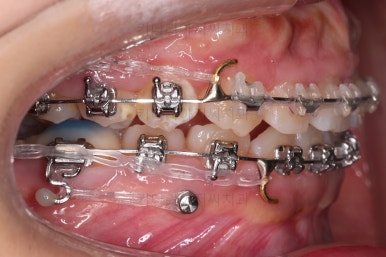

앞니쪽에는 미니스크류를 식립했는데요.

과개교합 개선, 교합 개선, 거미스마일(잇몸웃음) 개선 등 여러 가지 목적을 동시에 달성할 수 있어요.

윗니가 어느 정도 가지런해지면 아랫니도 장치가 들어갑니다.

위쪽은 미니스크류 위치를 바꿔줘 교합을 맞춰주고요.

아래쪽은 마찬가지로 미니스크류를 비대칭으로 식립해서 어금니를 당겨줍니다.